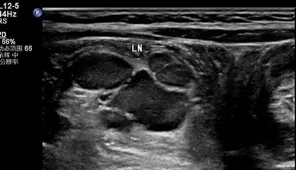

超声作为评估淋巴结最便捷、最直观的检查,能够快速评估淋巴结的形态、结构和血流特征。

淋巴结作为外周免疫系统的核心,由皮质、髓质和包膜3部分组成,广泛分布于颈部、腋窝、腹股沟等淋巴回流区域。根据解剖位置,可分为易触及的浅表淋巴结和难触及的深部淋巴结。儿童淋巴结大小的评估应综合年龄、解剖部位等进行个体化判断。当颈部淋巴结长径>20mm或短径>10mm时;腋窝淋巴结短径>8mm;滑车上淋巴结>5mm;肠系膜区域淋巴结长径>15mm或短径≥8mm或同一超声切面显示有3个或更多聚集时,即可诊断。